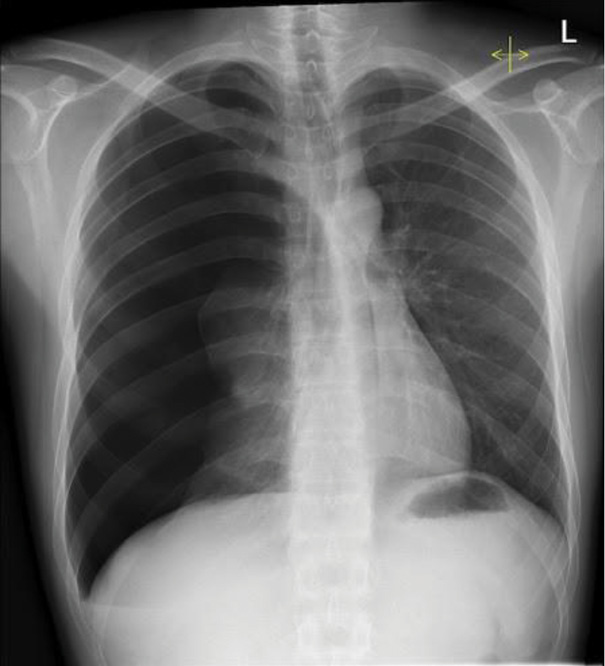

A portable chest radiograph confirmed a right-sided pneumothorax involving approximately 30% lung volume (Figure 1).